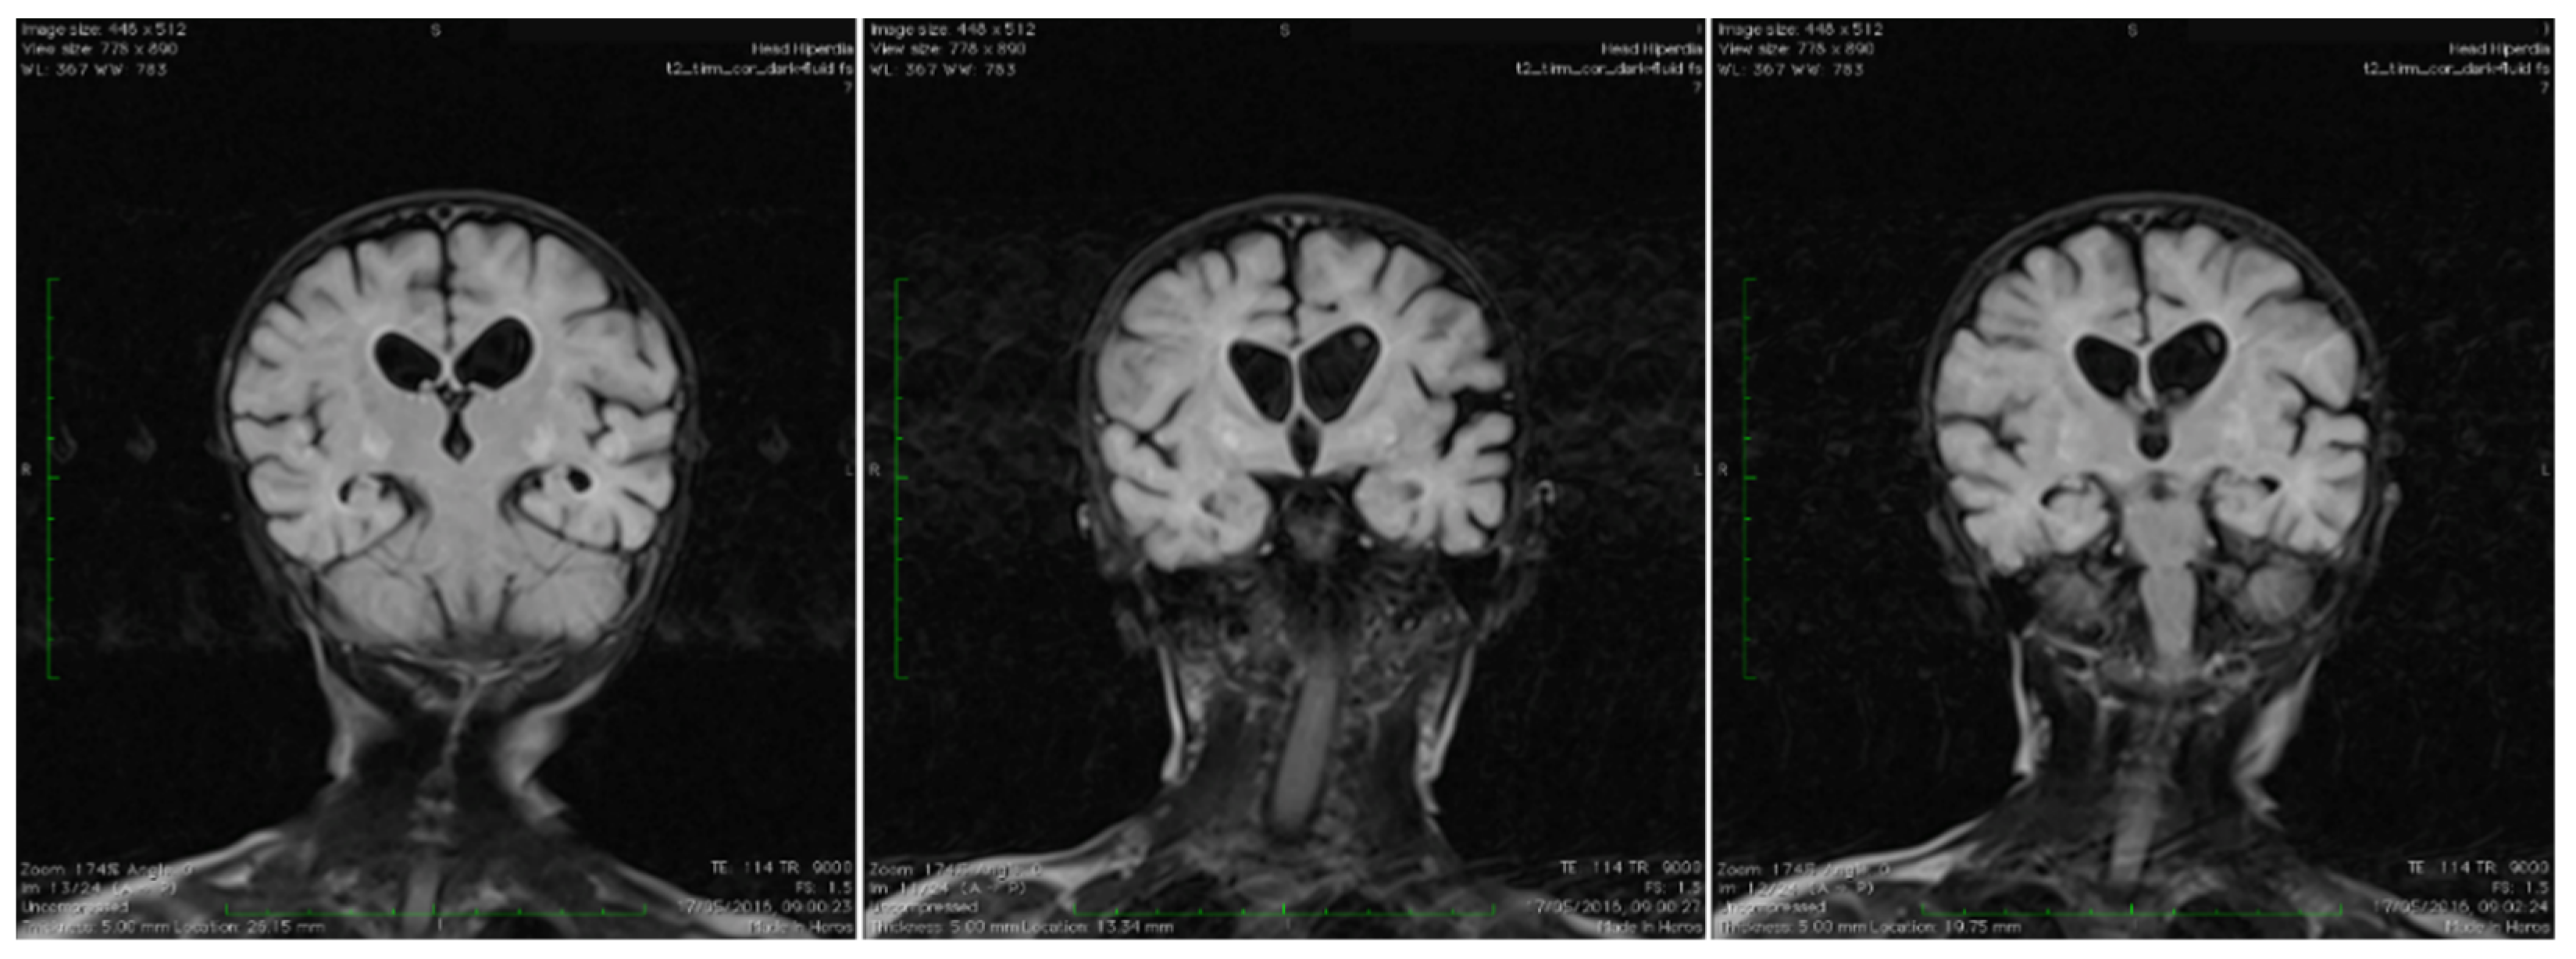

Brain magnetic resonance imaging (MRI) showed areas with increased T2-signal intensity and inhomogeneous fluid-attenuated inversion recovery (FLAIR) within the basal ganglia as well as cavitation at this level, with extensive diffuse white matter changes in the supratentorial area (leukodystrophy), and brain atrophy with subsequent widening of the perivascular space. Characteristic bilateral abnormal MRI signals in the brain were found (Figure 1).

Coronal T2 TIRM dark fluid MRI sequences revealing bilateral basal ganglia hyperintensities and cerebral atrophy.

Because of the characteristic pattern, a cranial MRI is recommended to be performed in such cases, as it can be itself diagnostic [2,15]. Moreover, conjugate eye deviation, hypotonia, and brain lesions in the basal ganglia and hyperlactatemia, may be found [2]. A characteristic brain MRI scan image exhibits bilateral and symmetrical T2 hyperintensity of the caudate nucleus, putamen, and globus pallidus, findings consistent with Leigh syndrome [2]. Similar findings were described in our case.